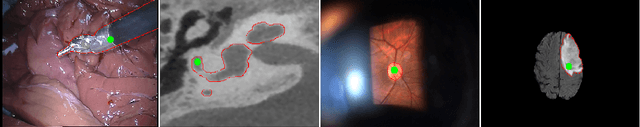

Abstract:Recent machine learning strategies for segmentation tasks have shown great ability when trained on large pixel-wise annotated image datasets. It remains a major challenge however to aggregate such datasets, as the time and monetary cost associated with collecting extensive annotations is extremely high. This is particularly the case for generating precise pixel-wise annotations in video and volumetric image data. To this end, this work presents a novel framework to produce pixel-wise segmentations using minimal supervision. Our method relies on 2D point supervision, whereby a single 2D location within an object of interest is provided on each image of the data. Our method then estimates the object appearance in a semi-supervised fashion by learning object-image-specific features and by using these in a semi-supervised learning framework. Our object model is then used in a graph-based optimization problem that takes into account all provided locations and the image data in order to infer the complete pixel-wise segmentation. In practice, we solve this optimally as a tracking problem using a K-shortest path approach. Both the object model and segmentation are then refined iteratively to further improve the final segmentation. We show that by collecting 2D locations using a gaze tracker, our approach can provide state-of-the-art segmentations on a range of objects and image modalities (video and 3D volumes), and that these can then be used to train supervised machine learning classifiers.

Abstract:Many recent machine learning approaches used in medical imaging are highly reliant on large amounts of image and ground truth data. In the context of object segmentation, pixel-wise annotations are extremely expensive to collect, especially in video and 3D volumes. To reduce this annotation burden, we propose a novel framework to allow annotators to simply observe the object to segment and record where they have looked at with a \$200 eye gaze tracker. Our method then estimates pixel-wise probabilities for the presence of the object throughout the sequence from which we train a classifier in semi-supervised setting using a novel Expected Exponential loss function. We show that our framework provides superior performances on a wide range of medical image settings compared to existing strategies and that our method can be combined with current crowd-sourcing paradigms as well.